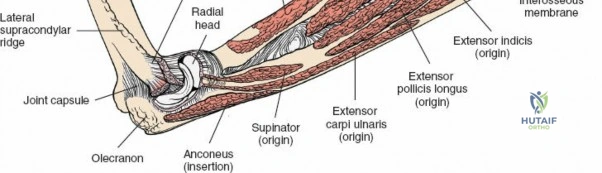

The radius and ulna function together as a highly coordinated articular quadrangle. The proximal radius consists of the radial head, which articulates with the capitellum; the radial neck; and the bicipital tuberosity, which serves as the insertion site for the biceps brachii tendon. The biomechanics of the forearm dictate that the radius rotates around the stationary ulna during pronation and supination. The normal lateral curvature of the radius—the radial bow—is critical for this rotational clearance. Any surgical approach to the proximal radius must allow for the precise restoration of this bow, as even a minor malreduction can lead to profound deficits in forearm rotation.

The posterior interosseous nerve is the single most important structure left vulnerable during exposure of the proximal radius. A branch of the radial nerve, the PIN dives into the supinator muscle through the Arcade of Frohse. It travels obliquely and spirally around the radial neck and proximal shaft within the substance of the supinator. In approximately 25% of patients, the nerve comes into direct contact with the posterior periosteum of the radial neck. Therefore, any blind placement of retractors around the posterior aspect of the proximal radius is strictly contraindicated, as it can easily crush the nerve against the bone, resulting in devastating loss of finger and thumb extension.